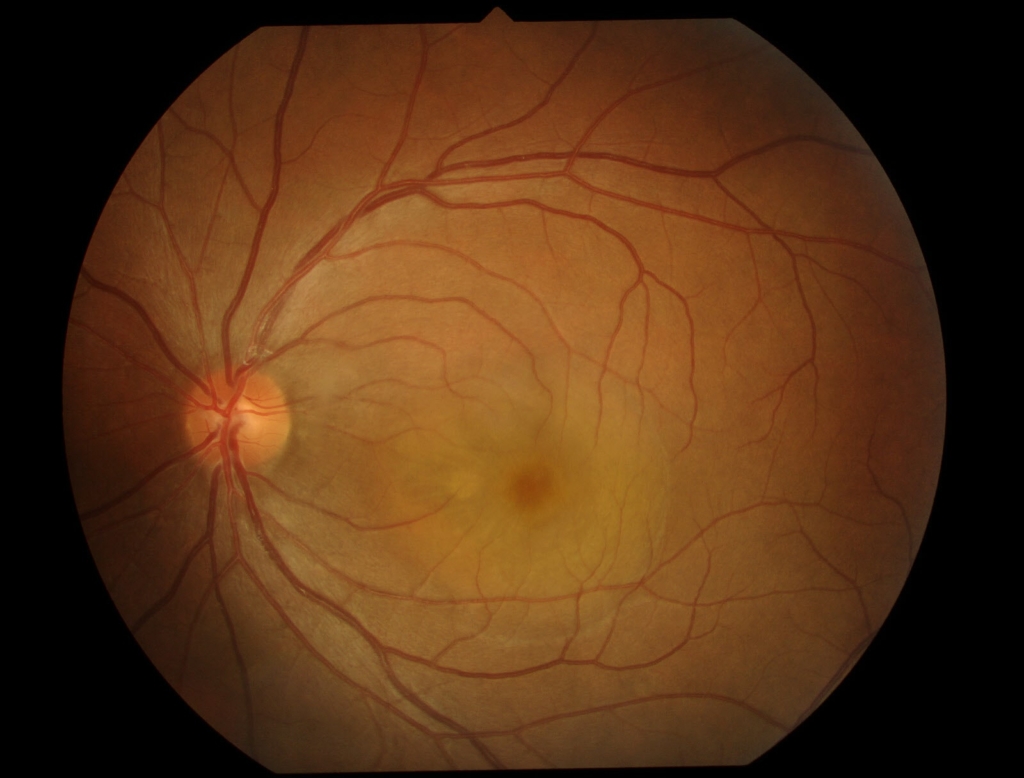

黄斑部に円形病巣がみられ、その鼻側縁に黄白色病巣がみられる。